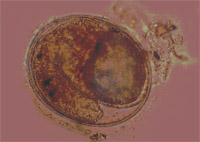

Hình ảnh con sán lá gan thu được ở bệnh nhân xã An Mỹ |

- Để xác định chính xác sán lá gan nhỏ ký sinh ở người, ngoài việc xét nghiệm phân tìm trứng, chúng tôi đã tiến hành điều trị cho bệnh nhân bằng thuốc đặc hiệu Pra ziquantel !important; sau đó thu hồi phân để đãi phân tìm sán. Kết quả đãi phân ở 35 bệnh nhân điều trị thu hồi được 331 con sán.

- Sau khi thu hồi sán lá gan nhỏ ở các vật chủ mèo nuôi, mèo gây nhiễm và ở người, chúng tôi đã xử lý và ép nhuộm làm tiêu bản định loại. Kết quả định loại theo các tiêu chuẩn hình thái học cho thấy tất cả sán lá gan thu hồi ở các vật chủ trên đều là loài sán lá gan nhỏ Opisthor chis viverrini.

Kết quả định loại hình thể học của chúng tôi đã được GS-TSKH Nguyễn Thị Lê, Viện Khoa học Việt Nam kiểm chứng đúng tên loài và được báo cáo nghiệm thu tại Hội đồng chấm luận án Tiến sỹ Y học cấp Nhà nước năm 2000. Loài sán này tiếp tục được kiểm chứng bằng kỹ thuật PCR của Viện Khoa học Việt Nam năm 2003 đều thống nhất kết quả là loài sán lá gan nhỏ Opisthor chis viverini.